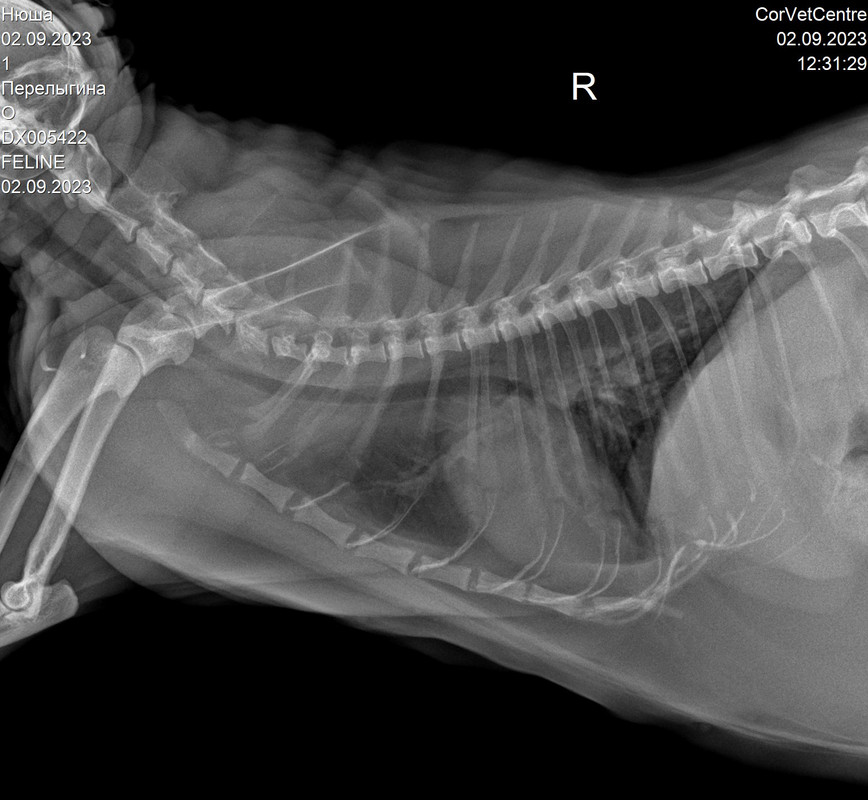

Истончение костей у кошек: причины и решения

Раздел: Мудрость в объективе